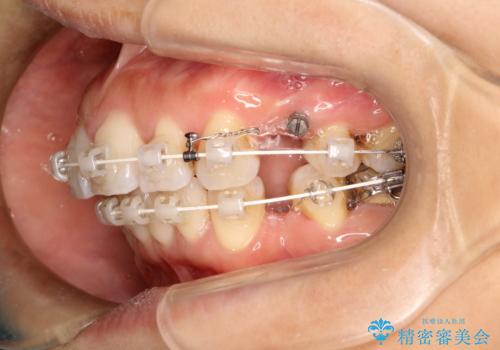

- 矯正装置

- 審美装置

- 上下の歯のがたつきを主訴に来院されました。

上下の前歯の叢生とかみ合わせが深い過蓋咬合という状態でした。

上下左右の歯を1本ずつ抜歯して、ワイヤーにて矯正を行いました。